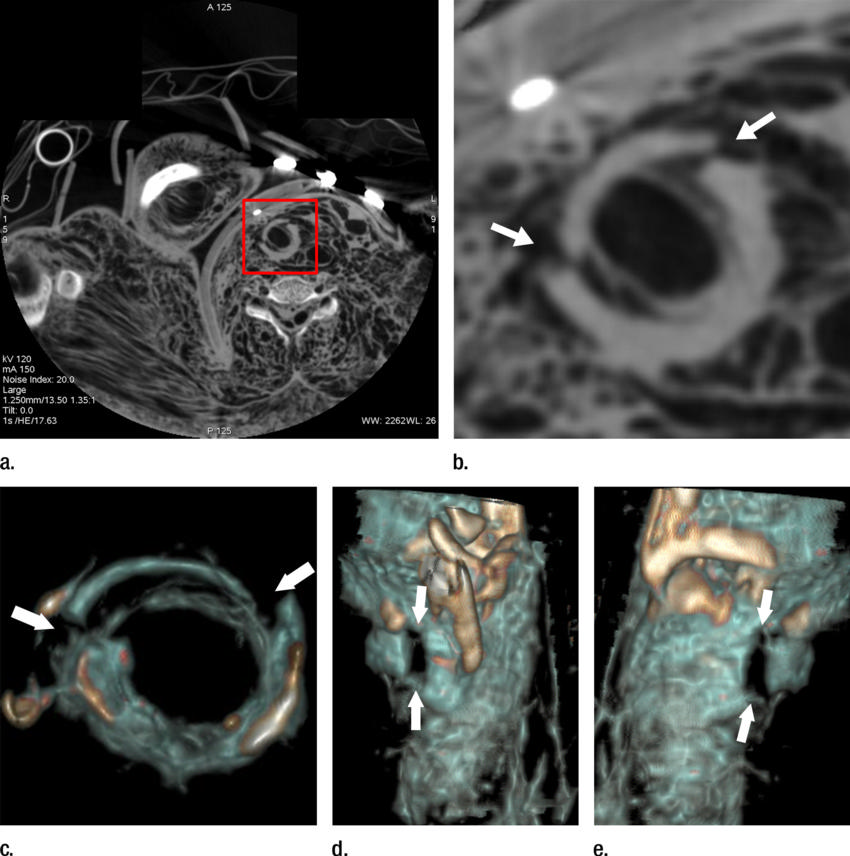

High-res (TIF) version

Figure 3. (a) Postmortem CT and (b–d) and arterial phase postmortem CT angiography images in a 59-year-old woman who died of internal exsanguination shortly after Whipple surgery. (a) A large left-sided hemothorax with mediastinal shift to the right. During the surgery, supraceliac clamping of the abdominal aorta was performed to stop intraperitoneal bleeding. The clamp was later loosened but left in place (arrow in b). The fatal hemothorax was caused by hemorrhage from the left 11th intercostal artery, which was torn near its origin from the aorta just above the diaphragm during placement of the clamp. The contrast media extravasation from the artery’s origin, reaching cranially into the thorax (arrows in b, c, and d), is displayed on arterial phase postmortem CT angiographic images (c and d). This finding may have been difficult to detect at autopsy because of the small size and location of the vessel. In this case it could not be displayed at autopsy because of large amounts of intraperitoneal and intrathoracic clotted blood, and multiple previous abdominal operations with extensive scar tissue formation and adhesions.